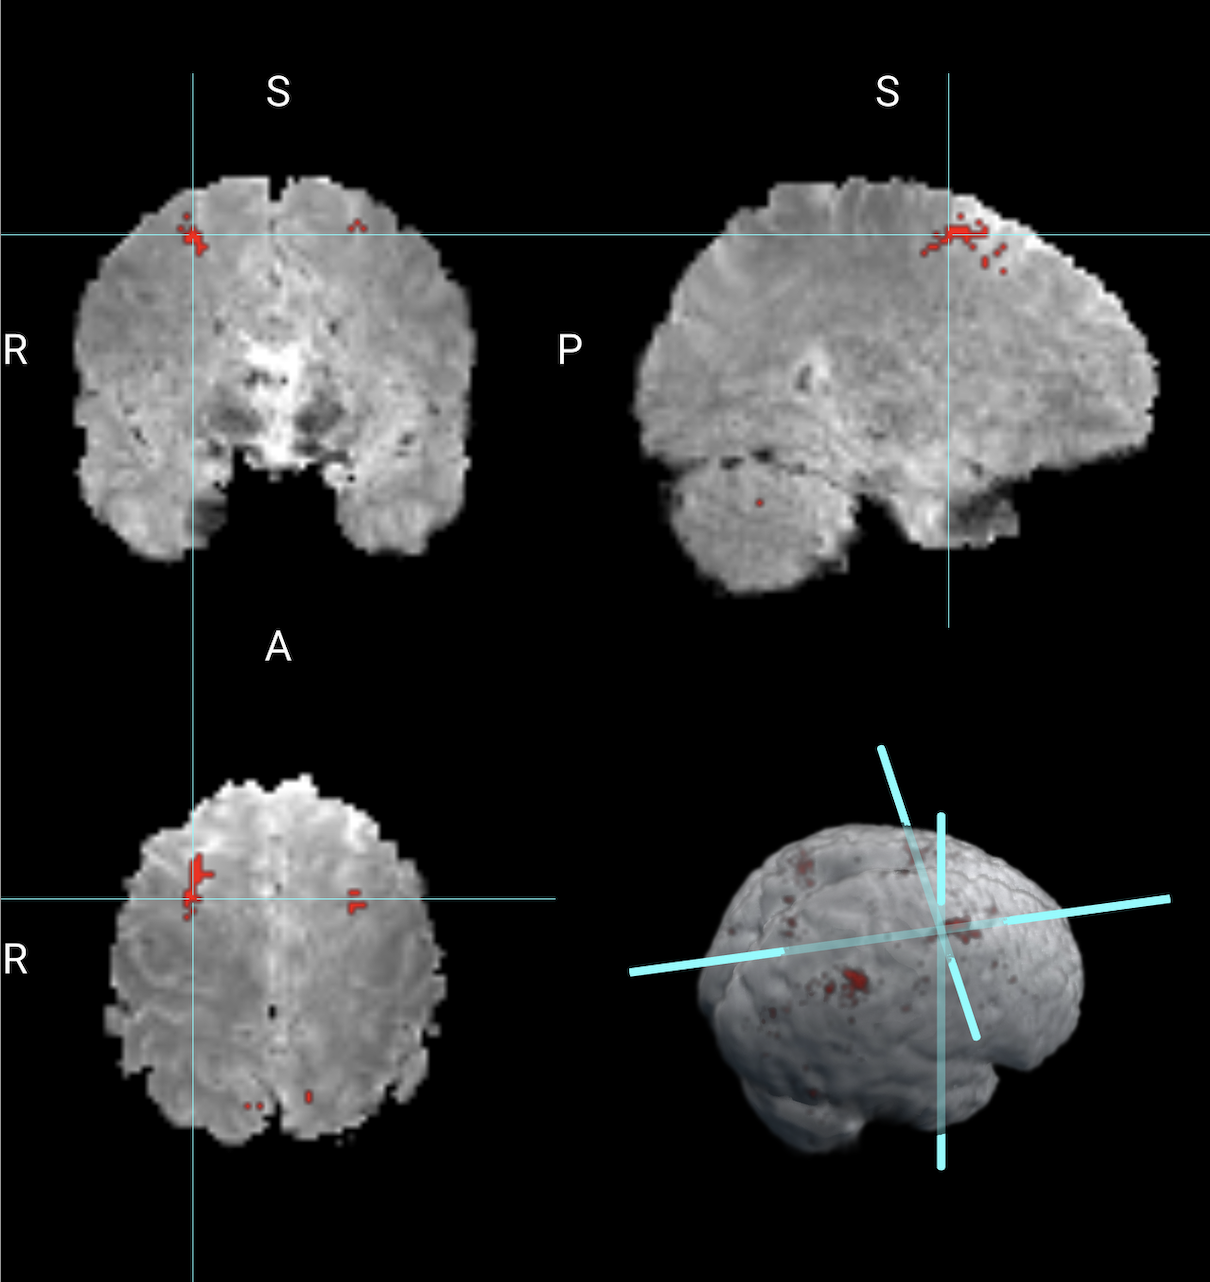

Next, we compare the results obtained from the Bayesian CP tensor basis approach with the results obtained from the Statistical Parametric Map (SPM) software [6]. We ran both the first and the second-level analysis in SPM with parameter settings to reflect no spatial normalization and an AR(1) noise component. The results for the Average of 2 back versus 0 back contrast are displayed in Figure 4. The two largest clusters were sizes 64 and 58 voxels, respectively. Overlaid onto the template is a mask with all significant voxels based on a voxel-level threshold that controls for the family-wise error rate of 0.05. Inspecting Figure 4 reveals that this SPM voxelwise model only capture small parts of the parietal and frontal lobe and has significant less power than the CP tensor basis approach.

Refer to caption

Figure 4: Working Memory contrast of 2back versus 0back obtained from SPM.